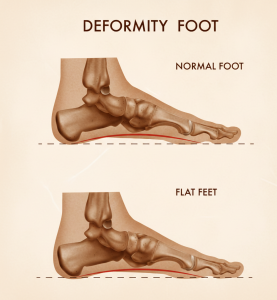

Evet, düz tabanlık (pes planus) diz ağrısına neden olabilir. Bunun nedeni, ayağın zeminle temas şeklinin değişmesiyle birlikte tüm alt ekstremite biyomekaniğinin etkilenmesidir.

Düz tabanlık dizleri nasıl etkiler?

Düz tabanlıkta ayağın iç kavsi çöker ve ayak yere basarken aşırı pronasyon oluşur. Bu durum zincirleme bir etki yaratır:

Ayak içe doğru fazla döner

Tibia (kaval kemiği) iç rotasyona zorlanır

Diz ekleminde yük dağılımı bozulur

Diz kapağı (patella) üzerindeki stres artar

Sonuç olarak diz eklemi normalden farklı bir yüklenmeye maruz kalır.

Düz tabanlık yürüyüşü nasıl etkiler?

Düz tabanlık yürüyüşü nasıl etkiler?

Düz tabanlık (pes planus), ayak iç kavsinin yeterince oluşmaması veya yük altında çökmesiyle ortaya çıkar ve yürüyüş mekaniğini doğrudan etkiler. Ayak, normalde yürüyüş sırasında hem şok emici hem de itici bir yapı gibi çalışırken, düz tabanlıkta bu denge bozulur.

Düz tabanlıkta yürüyüş nasıl değişir?

Düz tabanlıkta yürüyüş sırasında şu değişiklikler görülür:

Aşırı içe dönme (pronasyon): Ayak yere bastığında gereğinden fazla içe çöker

Şok emiliminin bozulması: Yük diz, kalça ve bele daha fazla aktarılır

İtiş gücünün azalması: Parmaklardan yerden itme zayıflar

Yürüyüşte dengesizlik: Adım uzunluğu ve ritmi değişebilir

Bu durum zamanla daha fazla enerji harcanmasına ve çabuk yorulmaya neden olur.